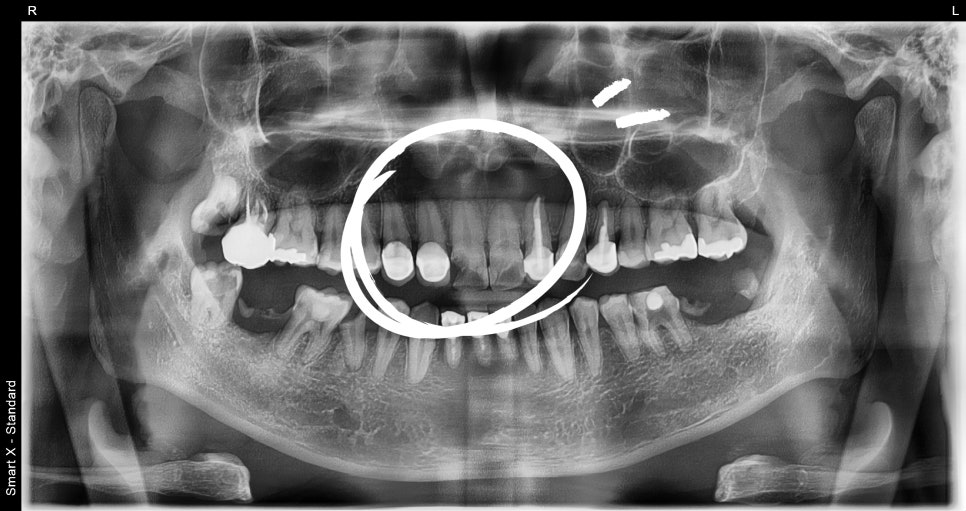

Diagnosis result: Cyst found at the root of tooth #11

When we examined the inside of the front tooth that seemed to have only a simple fracture,

a large cyst (periapical cyst) had formed in the root area of tooth #11,

and overall, there was extensive tooth damage requiring treatment.

✅ Although it looked like a small fracture on the outside,

✅ extraction was unavoidable internally,

✅ and cyst removal with immediate implant surgery was necessary.

📸 Before surgery

– Cystic lesion in the periapical area